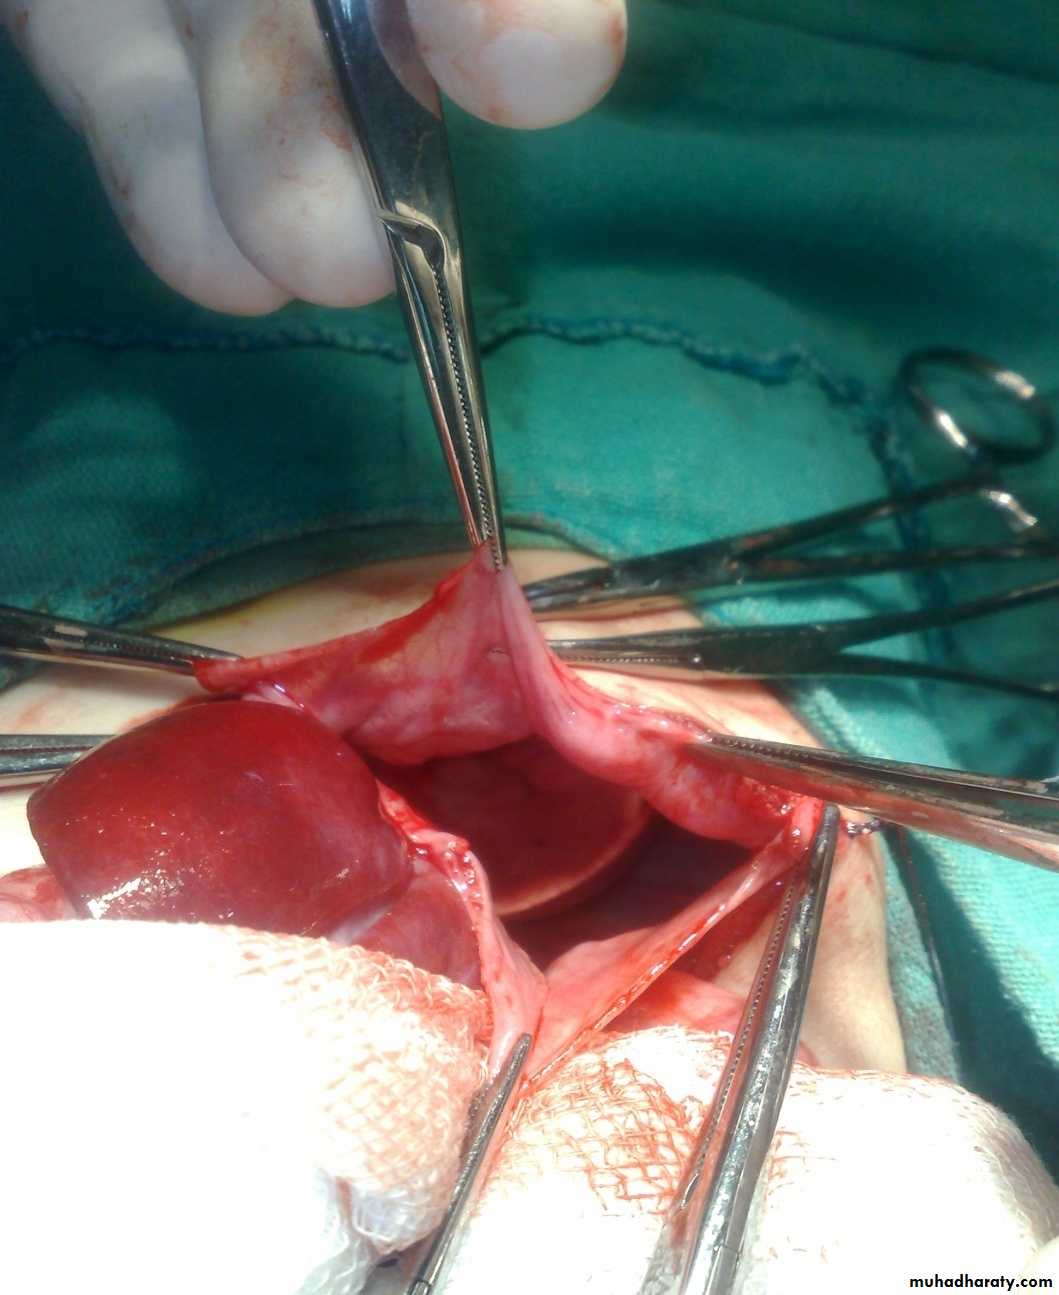

Scaphoid abdomen

Subcostal incision

content

Defect=sac